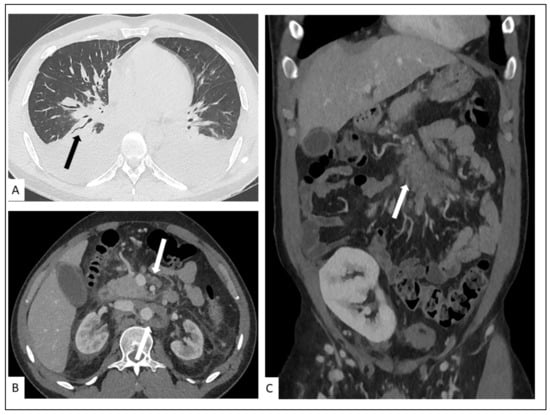

5.1. Pulmonary KS

5.2. Hepato-Splenic KS

5.3. Other Visceral Involvement